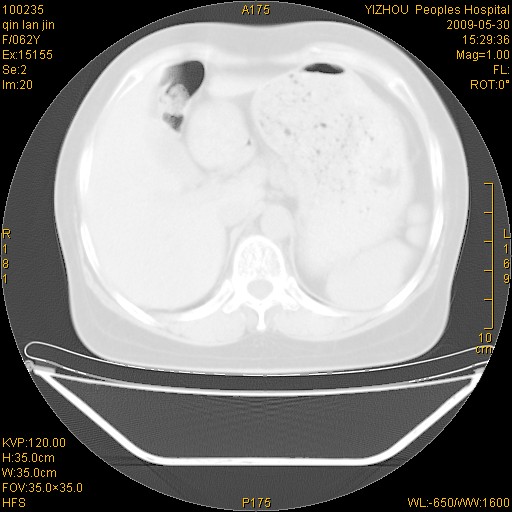

标题: CT20268:肺泡癌?间质性肺炎? [打印本页]

标题: CT20268:肺泡癌?间质性肺炎?

女,62岁,近二年经常咳嗽,近二个月,消瘦、乏力。

弥漫性双肺间质纤维化。

两肺弥漫性间质性病变(间质性肺炎伴肺间质纤维化?)。

弥漫性双肺间质纤维化

纵隔淋巴结大,须排外癌性淋巴管炎